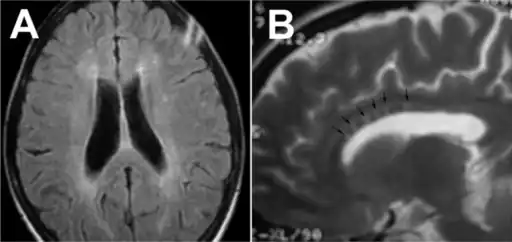

Susac syndrome- a)Deep white matter involvement of brain b)large central callosal snowballs

In a recent analysis (Susac et al., 2003), MRI images from 27 patients fulfilling the diagnostic criteria of Susac's syndrome were reviewed. Multifocal supratentorial lesions were present in all patients. Most lesions were small (3 to 7 mm), though some were larger than 7 mm. All 27 patients had corpus callosum lesions. These all had a punched-out appearance on follow up MRI. Though most commonly involving white matter, many patients also had lesions in deep grey matter structures, as well as leptomeningeal enhancement. Multiple sclerosis (MS) and acute disseminated encephalomyelitis (ADEM) can mimic the MRI changes seen in patients with Susac's syndrome. However, the callosal lesions in Susac's syndrome are centrally located. In comparison, patients with MS and ADEM typically have lesions involving the undersurface of the corpus callosum. Deep gray matter involvement commonly occurs in ADEM but is very rare in MS. Leptomeningeal involvement is not typical of either MS or ADEM. What this means is that if 10 lesions are found in the brain of an MS patient, a lesion may be found in the corpus callosum. If you have 10 lesions in a Susac patient, more than half will be in the corpus callosum.